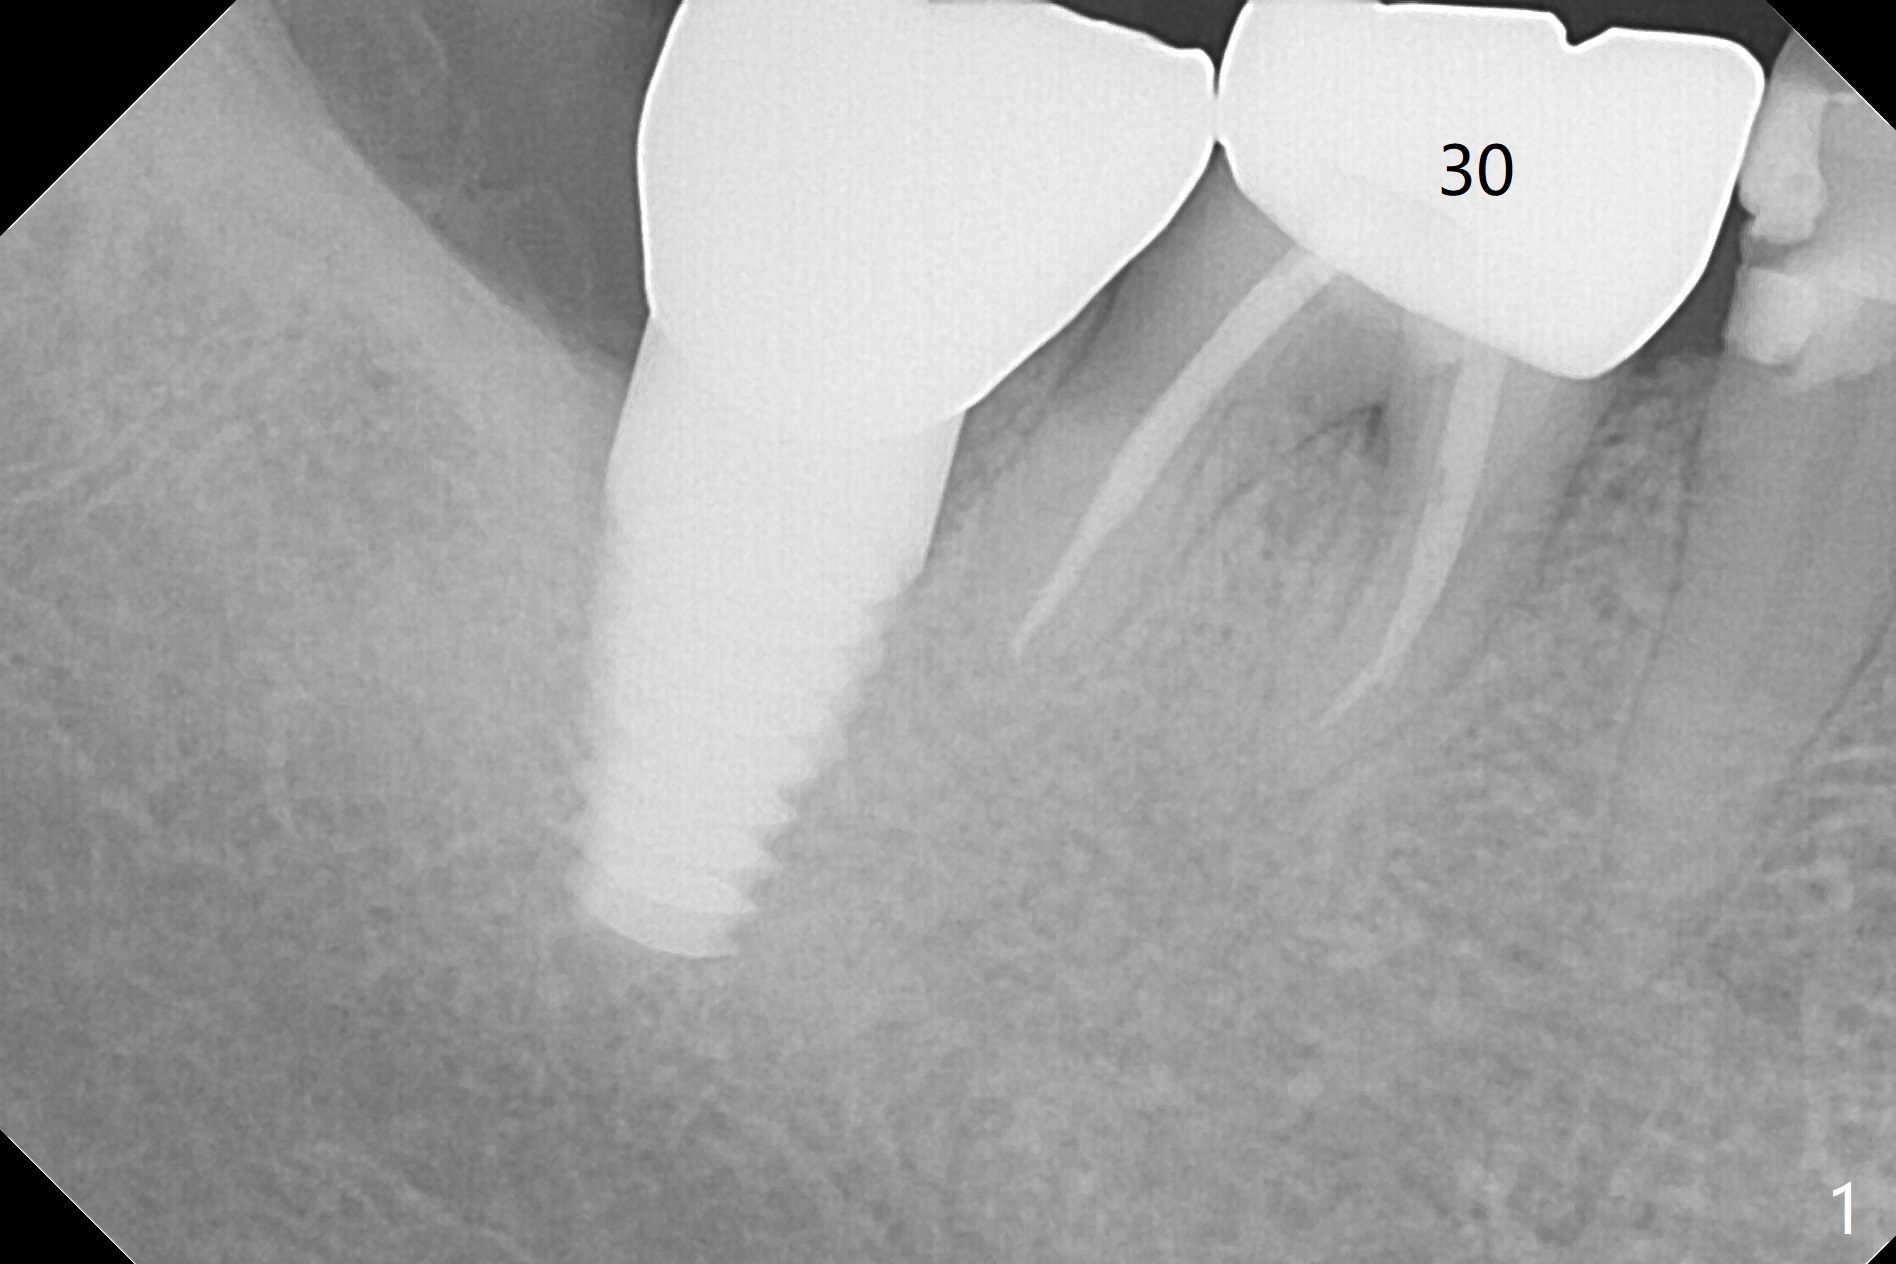

A 67-year-old woman masticates on the right side (Fig.1 (5 years post #30 RCT), as compared to Fig.4,6). One year and 6 months later, there is a fistula mesiobuccal to the tooth #30 (Fig.2 >,4) with mesial root fracture (Fig.3 >). Impression is taken for guide; a 5x11.5 mm implant will be placed slightly distal and lingual to the center of the septum (Fig.5).